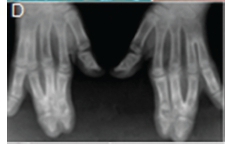

A diagnosis of Apert syndrome was made. Apert syndrome is a rare developmental condition characterized by premature cranial synostosis and resultant growth disturbances. Signs of Apert syndrome include a peaked and vertically elongated head, widespread bulging eyes, and a protuberant frontal region with an anteroposterior ridge overhanging the frontal eminence (Figure A). The palate is high, arched and occasionally cleft (Figure B). There is hypoplasia of the maxilla with relative prognatism of the mandible. Dental malocclusions with crowding and delayed dental eruption in the maxilla are common (Figure C). The facial angle is exaggerated; the nose is small and has been compared to a parrot's beak in appearance. Hypertelorism, exophthalmos and divergent strabismus are often present; sometimes with blindness. Spina bifida has been recorded in some patients. Syndactyly of the hands and feet varies greatly. Hand films in Apert syndrome showing syndactyly with fusion of three fingers in both hands and webbing (Figure D). Syndactyly of the feet in the same patient is also discernible (Figure E) Note the tall (turricephalic) skull, open metopic suture, and faint beaten-silver appearance of the calvarium. Skull base and roof of the calvarium are flattened, with a noticeable beaten-silver appearance (Figure F). The 3-D CT reconstruction of the same patient showing hypoplastic maxilla with posterior cleft (Figure G) The patient may be retarded or of normal intelligence. Apert syndrome may be associated with advanced paternal age. The cardinal radiologic features of Apert syndrome are: Brachycephalic (reduced anteroposterior dimension of the skull with increased skull width). Turricephaly (occurrence of a skull with high vertical index), beaten silver appearance of the calvarium, absence of demonstrable cranial sutures in coronal dimension in young patients, hypoplastic maxilla and syndactyly of the hands and feet. Differential Diagnosis: Crouzon's disease, Pfeifer syndrome, Carpenter syndrome and Summit syndrome.